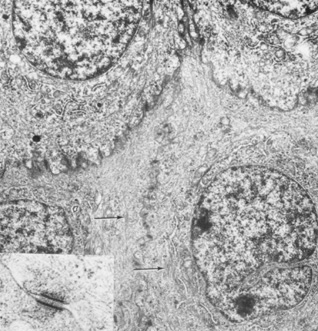

Wing cells are distinguished by a variety of polygonal shapes and by their large ovoid nuclei. The cells are roughly 12 to 15 μm in diameter, and their cytoplasm contains few rough endoplasmic reticulum cisternae, mitochondria, or Golgi's complexes. The large numbers of cytoskeletal tonofilaments are approximately 8 nm in length, and numerous interdigitations exist along the cell membranes.21 Desmosomal and gap junctions are seen between adjacent wing cells and between basal and apical cells (Fig. 7).

Fig. 7. Transmission electron micrograph of elaborate interdigitations between epithelial wing cell membranes. Desmosomes are seen along the cell walls, as well as intracellular tonofilaments (arrow). Intracellular rough endoplasmic reticulum, scattered mitochondria, and ribosomes are seen in addition to the prominent nuclei (13,800×). Inset: Desmosome junction (49,500×). (Courtesy of Drs. Rodrigues, Waring, Hackett, and Donohoo.)